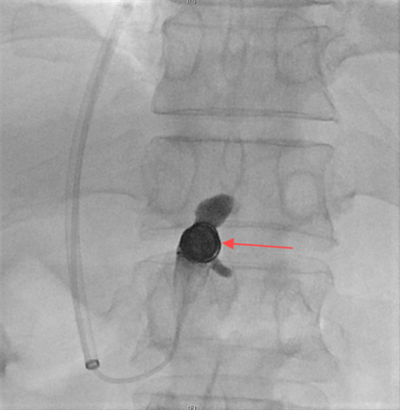

随后,赵扬程介入手术团队决定为患者施行经颈静脉肝内门体分流术(TIPS),术中经颈静脉入路精准植入8毫米覆膜支架,于肝静脉与门静脉间构建分流通道,同步完成食管胃底曲张静脉栓塞。术后门静脉压力由36厘米水柱降至20厘米水柱,出血立即停止,血红蛋白水平稳定回升。该手术在有效降低血管压力的同时维持肝脏血流灌注,为患者争取到后续治疗的宝贵时间窗。

图二:胃底静脉成功栓塞